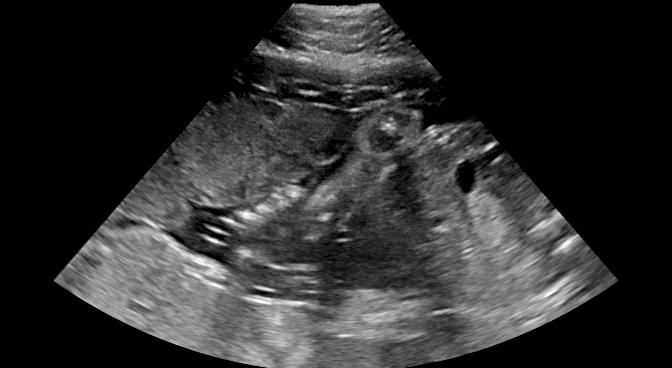

Sound-opaque occluders, including bones and calcified tissues, block the propagation of sound waves by strongly absorbing or reflecting sound waves during scanning. The regions behind these sound-opaque occluders return little to no reflections to the US transducer. Thus these areas have low intensity but very high acoustic impedance gradients at their boundaries (e.g. Fig. 1(a) left column). Reducing acoustic shadows and correct interpretation of images containing shadows rely heavily on sonographer experience. Experienced sonographers avoid shadows by moving the probe to a more preferable viewing direction during scanning or, if no shadow-free viewing direction can be found, a mental map is compounded with iterative acquisitions from different orientations.

![]() |

|

We propose a novel method based on convolutional neural networks (CNNs) to automatically estimate pixel-wise confidence maps of acoustic shadows in 2D US images. Our method learns an initial latent space of shadow regions from images consisting of multiple anatomies and with global image-level labels (“has shadow” and “shadow-free”), e.g. Fig. 1(a). The basic latent space is then estimated by learning from fewer images of a single anatomy (fetal brain) with coarse pixel-wise shadow annotations (approximately of the images with global image-level labels), e.g. Fig. 1(b). The resulting latent space is then refined by learning shadow intensity distributions using fetal brain images so that the latent space is suitable for confidence estimation of shadow regions. By using shadow intensity information, our method can detect more shadow regions than the coarse manual segmentation, especially relatively weak shadow regions.